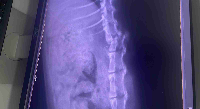

Olá,eu sou o gigio,e fui atacado por 5 cães,no condomínio onde fui abandonado,por conta disso perdi os movimentos das minhas perninhas, estou em um lar temporário pago com ajuda de doações,pois corria o risco de ser sacrificado a pauladas,agora preciso da sua ajuda para realizar a cirurgia da minha coluna, pois sinto muitas dores,e tenho muita chance de voltar a andar,o valor inclui, exames, cirurgia e fisioterapias,sou um gatinho cheio de gratidão ,

e vontade de viver,por favor me ajudem a voltar a correr e brincar novamente 🙌🏻🙌🏻